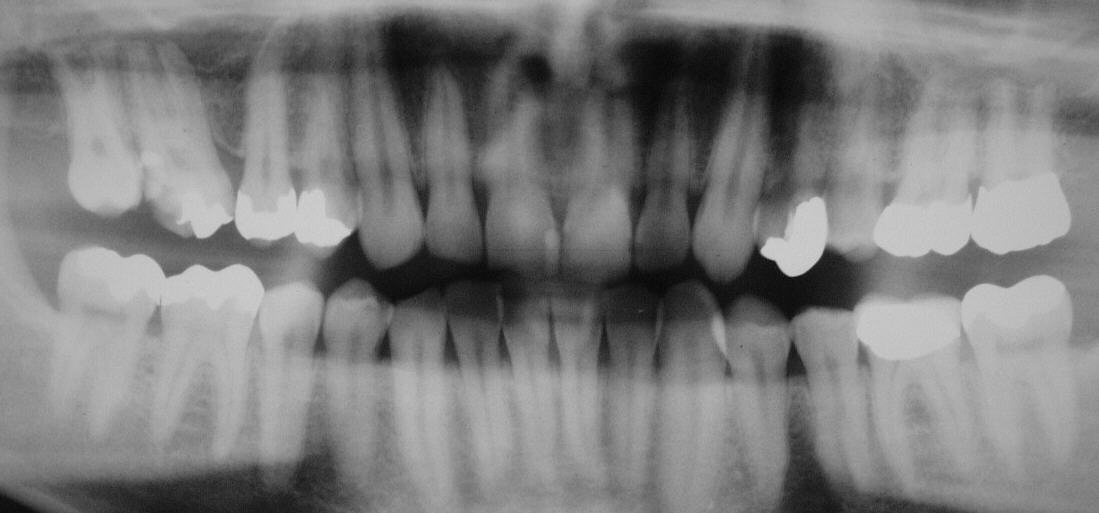

OPT aus November 2003 mit eröffnetem, aber nicht aufbereitetem 16, der seit mehreren Wochen homöopathisch behandelt wurde (Klick!)

Ausgangsbefund im Februar 2004 mit massiv beherdetem, fistelndem 46 mit  alter WF und deutlich beherdetem, nicht eröffnetem 25, der nach Angaben der Patientin seit 2 Jahren ununterbrochen fistelte (Klick!)